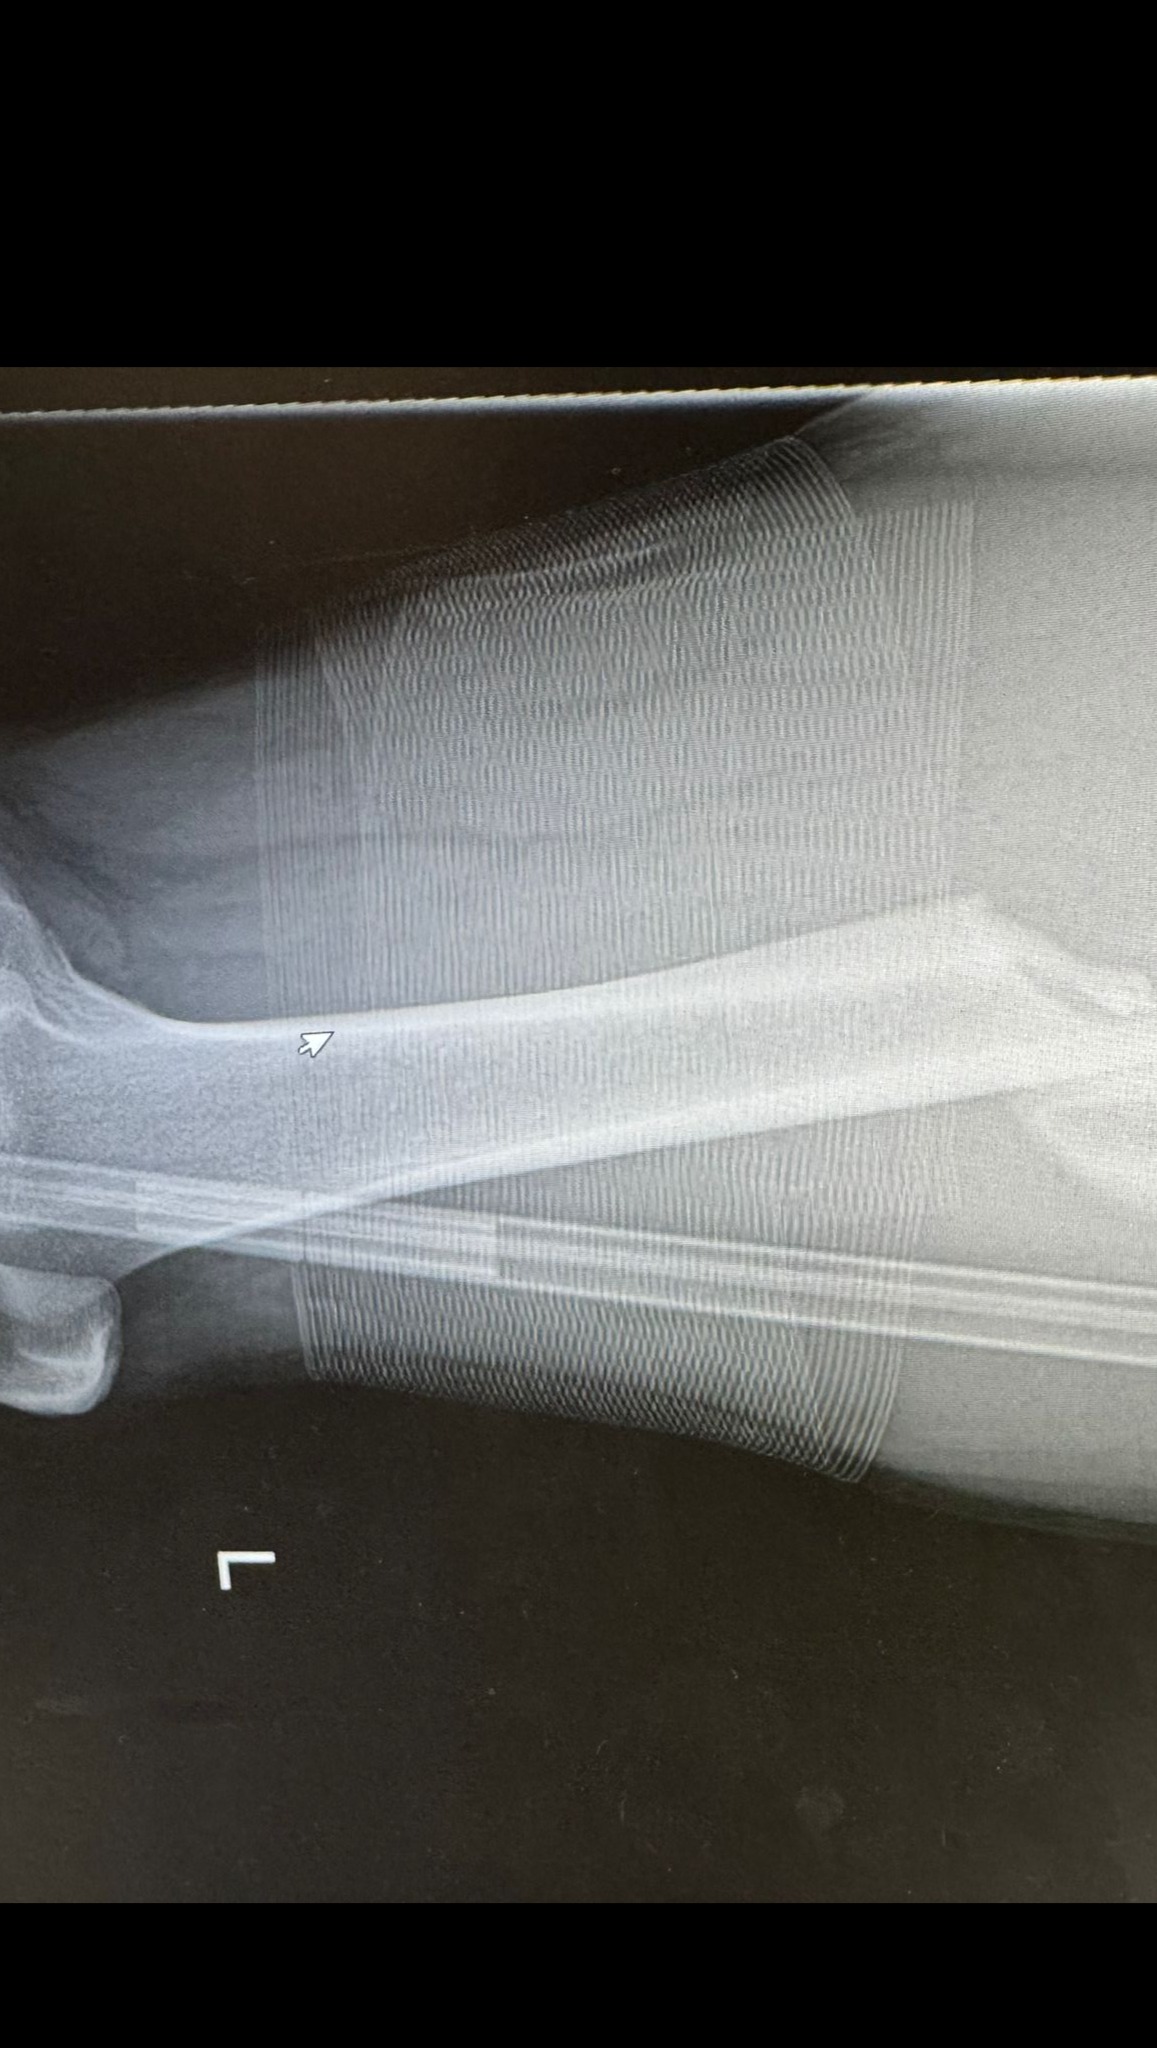

On 2nd November 2025, Cain was involved in a freak accident while playing football. After a long wait for emergency services, he was taken to hospital where it was confirmed he had suffered a serious femur break. Following surgery, Cain now faces months of rehabilitation and assisted walking, with hopes of returning to football in about a year.